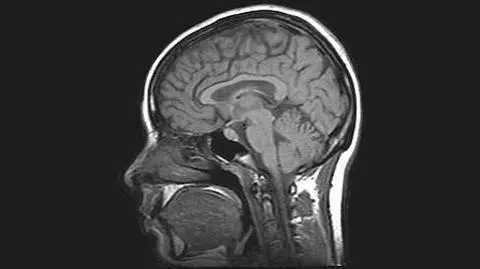

Takie skany mózgu pomoże analizować komputer

Opublikowana w środę praca opisuje wyniki pięciu osobnych badań przeprowadzonych z wykorzystaniem technologii funkcjonalnego rezonansu magnetycznego (fMRI). Skany mózgu wykonano zarówno u osób, które doświadczyły w przeszłości urazowego uszkodzenia mózgu, jak i takich, które go nie doświadczyły. Objęto nimi również osoby, u których depresja wystąpiła po urazie mózgu oraz osoby, u których wystąpiła ona w następstwie innych czynników. Badania przeprowadzono także na osobach z zespołem stresu pourazowego i bez niego. Łącznie grupa badawcza składała się z 273 osób.

Analiza wyników wykazała, że zarówno u osób, u których depresja rozwinęła się po urazowym uszkodzeniu mózgu i osób, u których choroba spowodowana była innymi czynnikami, z chorobą powiązane były te same obwody mózgu. Zdawały się jednak one działać w przeciwny sposób. Przykładowo, te same obwody, które u osób z depresją w następstwie urazu były nadaktywne, u osób z depresją spowodowaną innymi względami były niedoczynne.